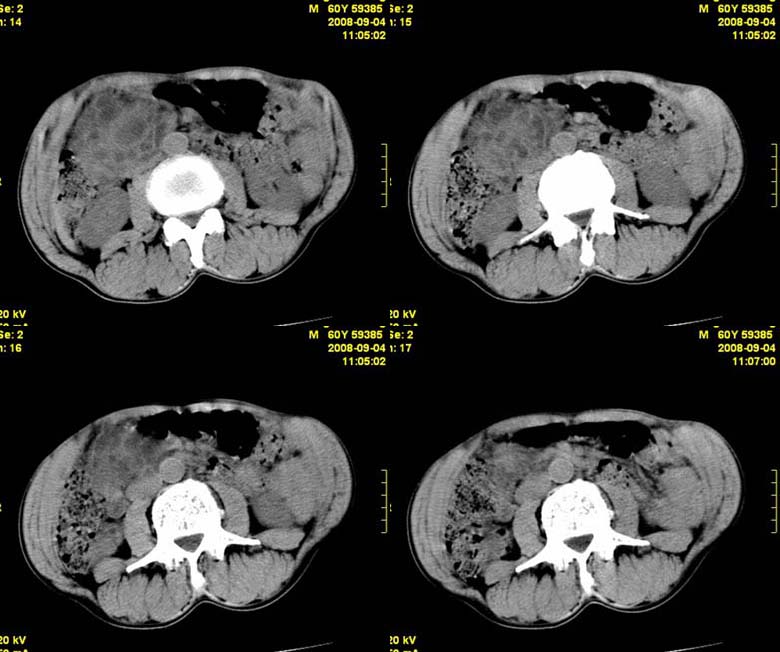

标题: CT15580:M60Y,胰腺病变,平扫+增强 [打印本页]

标题: CT15580:M60Y,胰腺病变,平扫+增强

患者,男, 60,既往有间歇腹痛病史多年,现右上腹痛,加重一月,伴右后背部疼痛,无黄疸,无发热。

胰腺炎,胰液滞留性假囊肿

考虑胰腺囊腺瘤或慢性胰腺炎可能性大

粘液性囊腺瘤

同意胰头部囊腺癌

胰头囊样增大不均匀强化,腺管扩张。结合病史首诊慢性胰腺炎、假性囊肿